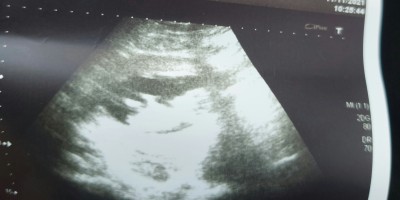

Bilen var mı sizce kız mı erkek mi

Erkeğe benzettim ama  hayırlısı olsun inşallah sağlıkla gelsin

Sanki erkek gibi ama 16.haftaya kadar bekleyin derim.

Erkek bence canim

Evet kuzum gorunusune gore benim.oglusumda boleydi kac haftalik canim

Çok teşekkür ederim. 12 haftalık

Çıkıntı var popo kısmında bende erkeğe benzettim ama tabiki zamanı geldiğinde doktorun en iyisini bilir  Rabbim sağlık la kucağına almayı nasip etsin inşallah

Erkek canim bencede

Erkek bence , görünen de yumurtalık gibi